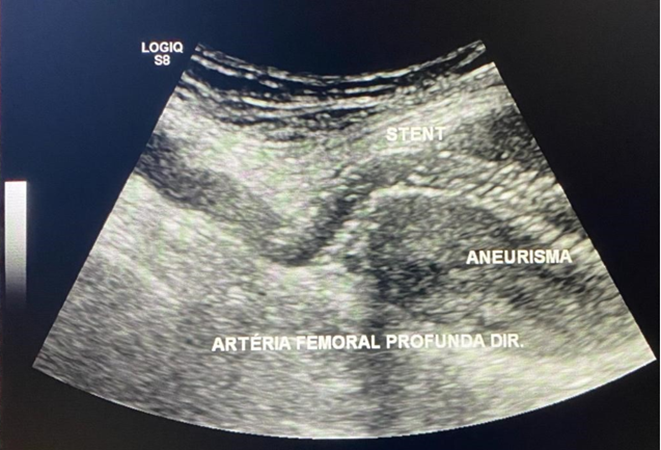

The patient was scheduled to undergo endovascular treatment of the deep femoral artery aneurysm. Under general anesthesia, a left common femoral artery was punctured guided with a duplex ultrasound., with a 6f 11cm sheath. We decided to use a contralateral access and perform the whole intervention percutaneously. After the puncture, the Perclose Proglide â was inserted, in order to preload and guarantee the sealing of the puncture. Then, a 0,035”260cm Terumo â was passed untiused to perform the crossing overl of the aorta, and a 9F 11cm sheath was placed through the left common femoral artery. The patient was heparinized with 5000UI intravenous in bolus., and the aorta was crossed with an internal mammary 6F catheter alongside the 0,035”260cm Terumo â. We performed a right limb arteriography to confirm the deep femoral artery aneurysm (Figure 3s 5 and 6). The deep femoral artery was properly catheterizedselected with a Headhunter catheter 5F. After this, and we changed the guidewire for an Amplatz 0,035”260cm, in order to place a 55cm 9F delivery system catheter until the origin of the right deep femoral artery. In the arteriography, we have identified a larger branch emerging from the first portion of the deep femoral artery, and we have decided to embolize this branch, to avoid endoleak type II, since it was a larger branch. The microcatheter Progreat â 2,7F alongside the microguidewire Avigo â was used to select the branch. We embolized this branch with Azur â coils 2 4x5, 6x10, 6x15 and 6x20 (figures 7 and 8). After the successful embolization, a covered self-expandable 9x100 Solaris â (Scitech Medical, Brasil) was placed under roadmap into the proximal and distal deep femoral artery aneurysm, and post dilatated with a 9x80 catheter balloon Oceanus â (figure 4 Figures 9 and 10). There were no endoleaks, and the deep femoral artery patency was identified. All the materials were removed, and we completed the final step of the perclose Proglide â puncture closing. The patient was transferred to the room, being discharged from the hospital two days after the surgery with no complications, femoral, popliteal and podal pulses present bilaterally, taking Aspirin 100mg / day and Clopidogrel 75mg/day. After 1 month the patient was evaluated, presenting no further symptoms, no palpable mass in the right groin, and was submitted to a Duplex Ultrasound (Figure 5s 11 and 12), that showed deep femoral artery patency, stent patency, reduction of the aneurysm sac and no endoleaks. Furthermore, after one year follow-up, the patient remained assymptomatic, with Duplex Ultrasound showing deep femoral and stent patency and no endoleaks. (Figure 6).

Figure 5: Duplex Ultrasound showing deep femoral artery patency, stent patency and no endoleaks at 1 month.

Figure 6: Duplex Ultrasound showing deep femoral artery patency, stent patency and no endoleaks at 1 year;